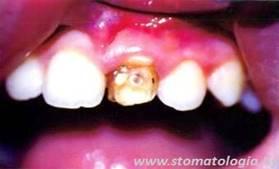

Итак, клинический пример:

Пациент Дима Г., 6.5 лет. Жалобы на боли от термических (даже теплая вода вызывала боль), химических (кислое – сладкое) и механических раздражителей в области прорезавшихся 36 и 46 зубов.

Объективно: частичная аплазия эмали по язычной поверхности и в области язычных бугров 36, 46 зубов. Реакция на воздух из пустера резко положительная, быстропроходящая. Результат обработки кариес-детектором отрицательный. Кстати, если делать реставрацию, то без анестезии никак нельзя. Было принято решение развести лечение на несколько этапов.

На первом, в день обращения, проводилось снижение чувствительности праймером GLUMA-DESENSITAJZER (фирма H.-KULZER) согласно инструкции. Единственное, что время аппликации препарата сократили примерно в полтора раза. Через три дня процедуру повторили. В итоге – практически полное снижение чувствительности пораженных зубов.

Далее, в третье посещение, спокойно и без всякой анестезии была проведена профчистка этих зубов и обработка поверхностей ПРАЙМ ЕНД БОНД–NT (фирма ДЕНТСПЛАЙ). Этап кондиционирования поверхностей исключили!!! После этого пораженные участки покрывались слоем текучего компомера и полимеризовались.

Весь этот этап занял в общей сложности не более 10 минут. Рабочее поле кофердамом не изолировалось.

В течение всего времени наблюдения никаких осложнений не отмечалось, сколов материала не было. В дальнейшем, в возрасте 12-13 лет будет проведена реставрация проблемных зубов с восстановлением их анатомической и функциональной целостности по всем правилам реставрационной технологии.